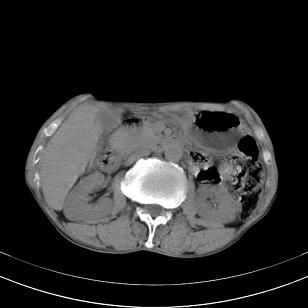

标题: 男,65岁,反复右上腹痛, [打印本页]

标题: 男,65岁,反复右上腹痛,

胃镜提示十二指肠占位